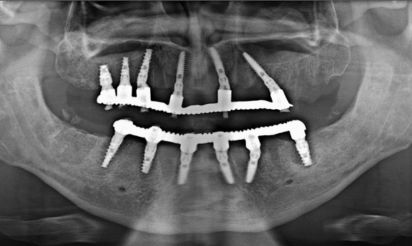

Case2 X Ray